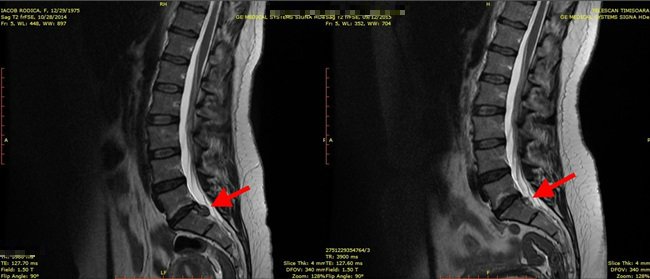

Hernie De Disc Rezolvata Fara Operatie Noutati Ozonoterapie Timisoara Clinica Medozon

Hernie De Disc Tratata Fara Bisturiu Tehnica Pldd Percutaneous Laser Disk Decompression Clinica De Neurochirurgie Timisoara